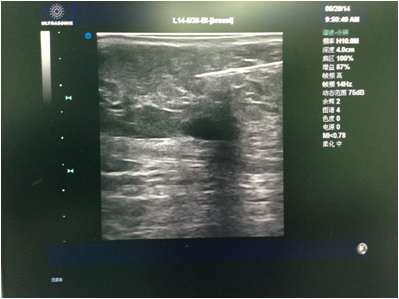

先由主刀医生行彩超检查,和患者确认及核对拟切除的目标病灶。消毒铺巾后医生在彩超引导下于表皮,手术路径及目标病灶周围注射局麻药(图1)。麻醉满意后于彩超引导下进旋切针到目标病灶下方,然后开始切除目标病灶(图2)。最后加压包扎,切除的病灶送病理检查(图3)。整个手术过程于局麻下完成,会有轻微疼痛,但一般程度不重。

图1 注射局麻药。图中黑色低回声为肿物,上方的白色条索为注射局麻药的针头。